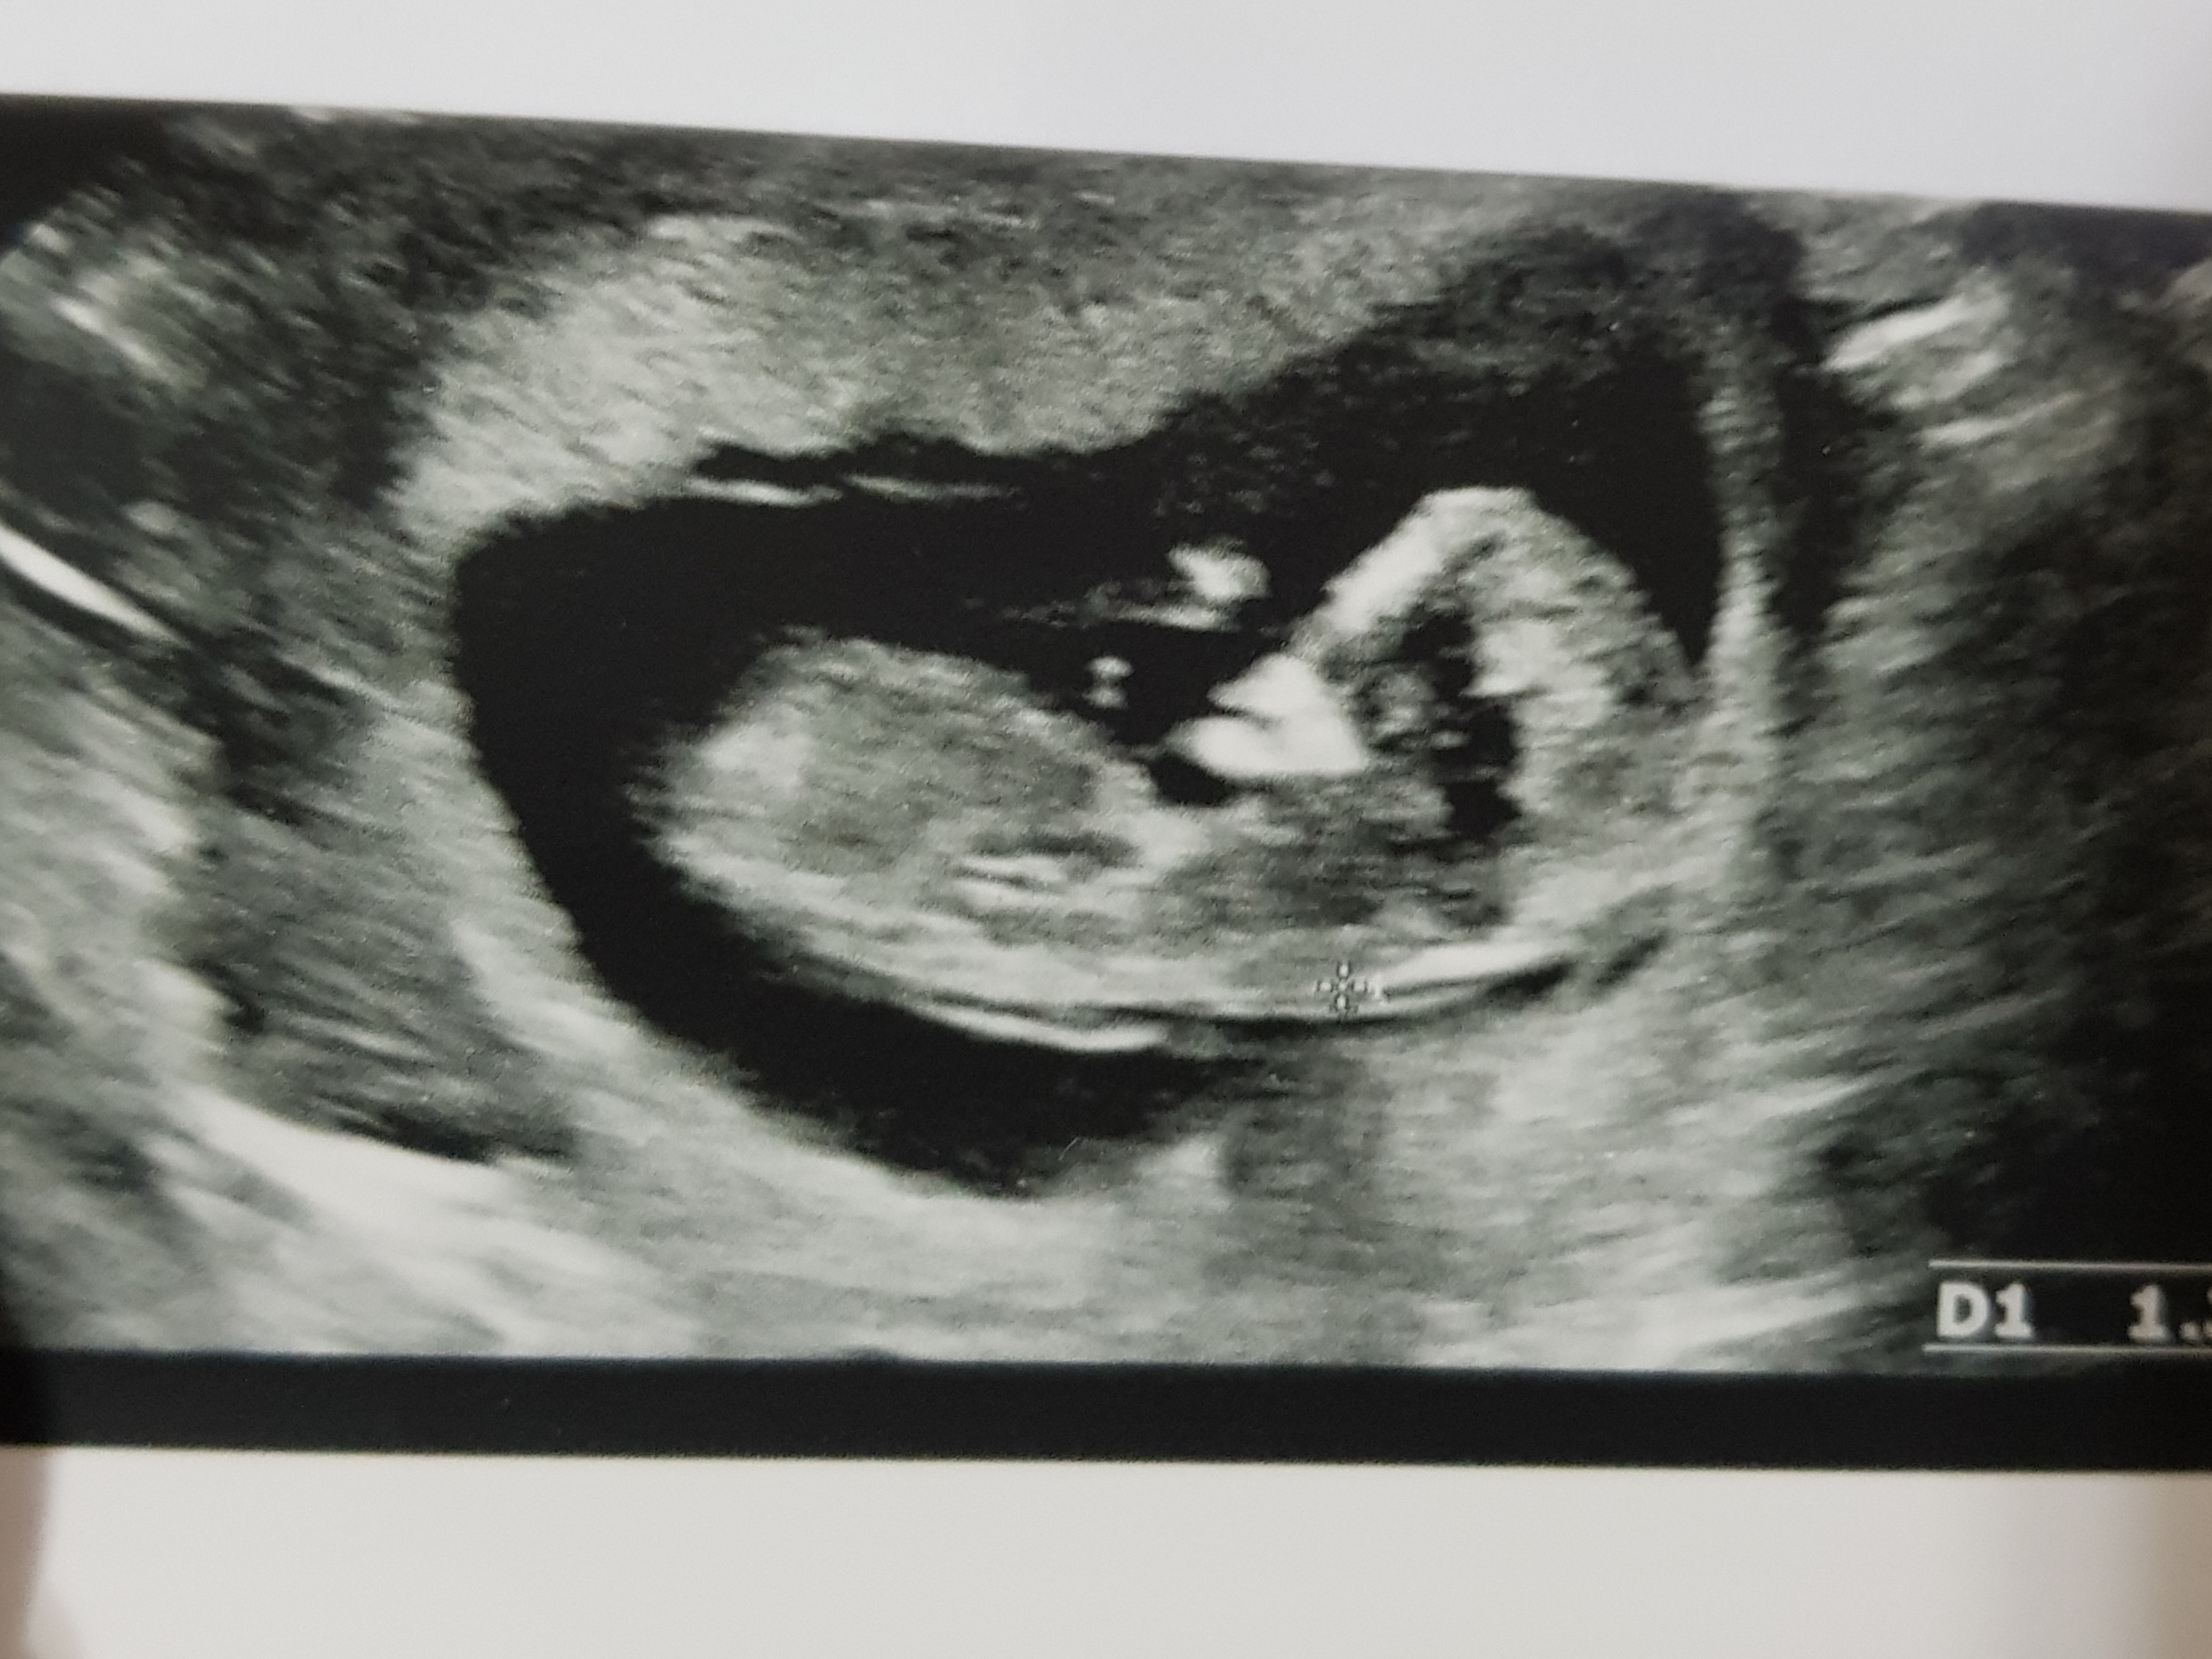

من برام فرقي نميكنه هرچب باشه سالم باشه ولي ميخوام باهاش حرف بزنم اسم بزارم روش ميگن ميفهمه و ميخوام ...

انشاالله سالموسلامت بیادتوبغلت اره آدم دوست داره سریع بدونه جنسیتو

دختره مطمئنم. بعدا بیا بگو چیشد

ضربان قلبش چقدر بود؟

مال شما پسر. بعدا بیا شما هم بگو

وای خدا دکتر گفت ۶۰ درصد دختر آخه